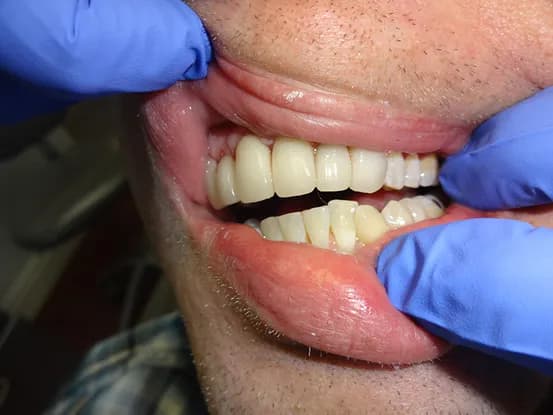

Case 3

35 year old male with extensive cervical decay resulting from diet high in sugars. 8 units of Porcelain crown & bridge performed. Missing tooth was eventually replaced with implant after photo was taken.